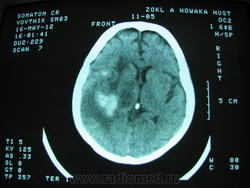

Никак не найду первичных "фото" , но динамика очень-очень положительная.

Нету здеся неопластического процесса - не правда-ли???